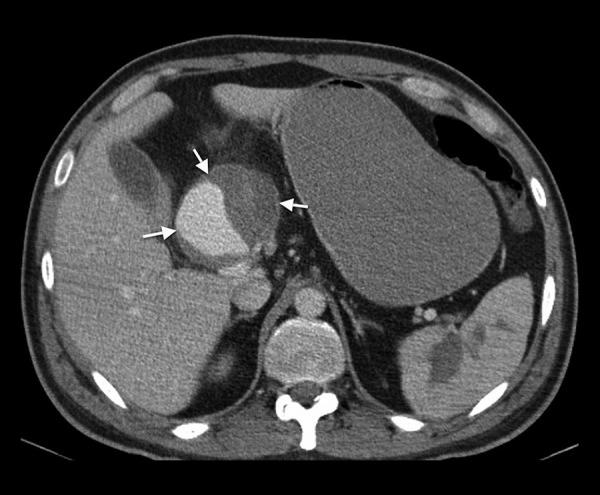

A man at the age of 34 years with blunt trauma dating back to 1.5 month was admitted to the emergency department of a hospital with hematemesis and epigastric tenderness. He also had a duodenal ulcer, blood in the gastric lumen and a large pseudoaneurysm that developed from the left hepatic artery. Soon after the diagnosis, the patient worsened and underwent distal gastrectomy and cholecystectomy that included removing the bleeding aneurysm.

一名34岁男性,1.5个月前遭受钝性创伤,因呕血和上腹部压痛入住一家医院的急诊科。他还患有十二指肠溃疡、胃腔内出血以及一个由左肝动脉形成的大假性动脉瘤。诊断后不久,患者病情恶化,接受了远端胃切除术和胆囊切除术,其中包括切除出血的动脉瘤。